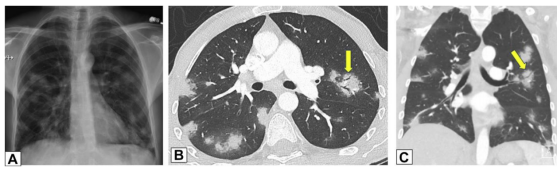

图源:Chest, 2022, 162(1):156-178.图3A为71岁男性,2011年7月因劳力性呼吸困难就诊,胸片显示右肺上叶实变。图3B为2012年6月再次检查显示右肺上叶异常已消失,左肺出现广泛实变。图3C为2013年6月,左肺病变消失,但右肺下叶出现新的实变。这些发现是典型的OP游走性表现。图源:Chest, 2022, 162(1):156-178.图3所示患者胸部CT可见磨玻璃影伴小叶间隔增厚和铺路石征的游走灶(图4)。由此可见,OP的实变可以发生在肺的任何部位,边界清晰或模糊,呈游走性特点。图源:Chest, 2022, 162(1):156-178.OP的实变可以呈局灶性、多发性和弥漫性,也可以表现为结节或肿块。图5所示患者为70岁女性,COVID-19确诊9个月后出现持续气促,CT平扫图像显示支气管血管周围多灶性肿块样实变。在类固醇治疗后症状显著改善,实变消退,推测诊断为OP。图源:Chest, 2022, 162(1):156-178.实变常伴支气管充气征,可伴散在的磨玻璃样低密度或小实质结节。以主要的或完全的磨玻璃低密度为表现者较少见。图6A所示为一名有甲状腺乳头状癌病史的47岁男性患者碘131治疗4个月后的CT平扫图像,可见右肺上叶支气管血管周围磨玻璃影。PET/CT扫描显示磨玻璃影代谢增高(图6B)。CT平扫图像显示左肺上叶新出现的磨玻璃影(图6C)。支气管活检结果与OP相符。图源:Chest, 2022, 162(1):156-178.图7为一名71岁男性患者因使用胺碘酮导致SOP的CT平扫图像,可见左肺广泛磨玻璃影,小叶间隔增厚(铺路石征)。磨玻璃低密度影合并小叶间隔增厚可表现为铺路征。